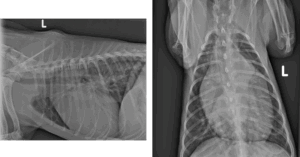

To further evaluate the condition, your veterinarian may suggest performing chest radiographs (Figure 1) to check for fluid buildup in the lungs, which can indicate heart failure resulting from excess blood shunting into the lungs. To confirm the diagnosis, your veterinarian may refer you and your pet to an American Board-Certified veterinary cardiologist (ACVIM – Cardiology) for an echocardiogram (a heart scan). This procedure enables direct visualization of the PDA, measurement of the heart chambers, and assessment of the PDA’s size and function. Furthermore, an echocardiogram can identify other congenital heart defects that may not be immediately apparent, as it is not uncommon for puppies or kittens to have multiple congenital abnormalities. This comprehensive information enables the veterinary cardiologist to recommend the most effective treatment for your pet with PDA.